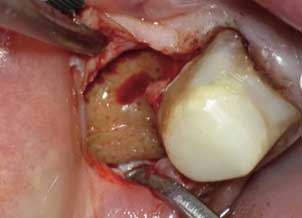

Silent inflammation due to root canal therapy, cavitation (avascular osteonecrosis) and titanium implants leads to immune system activation. The intraoral interference fields created by metals, NICOs, bacteria in root canal treated teeth produce highly toxic hydrogen sulfides (Thioether/Mercaptan), metals show cytotoxic, immunological and carcinogenic effects and NICOs (Neuralgia inducing osteonecrosis) consist of increased inflammatory mediators like RANTES, FGF-2 and IL-1ra.